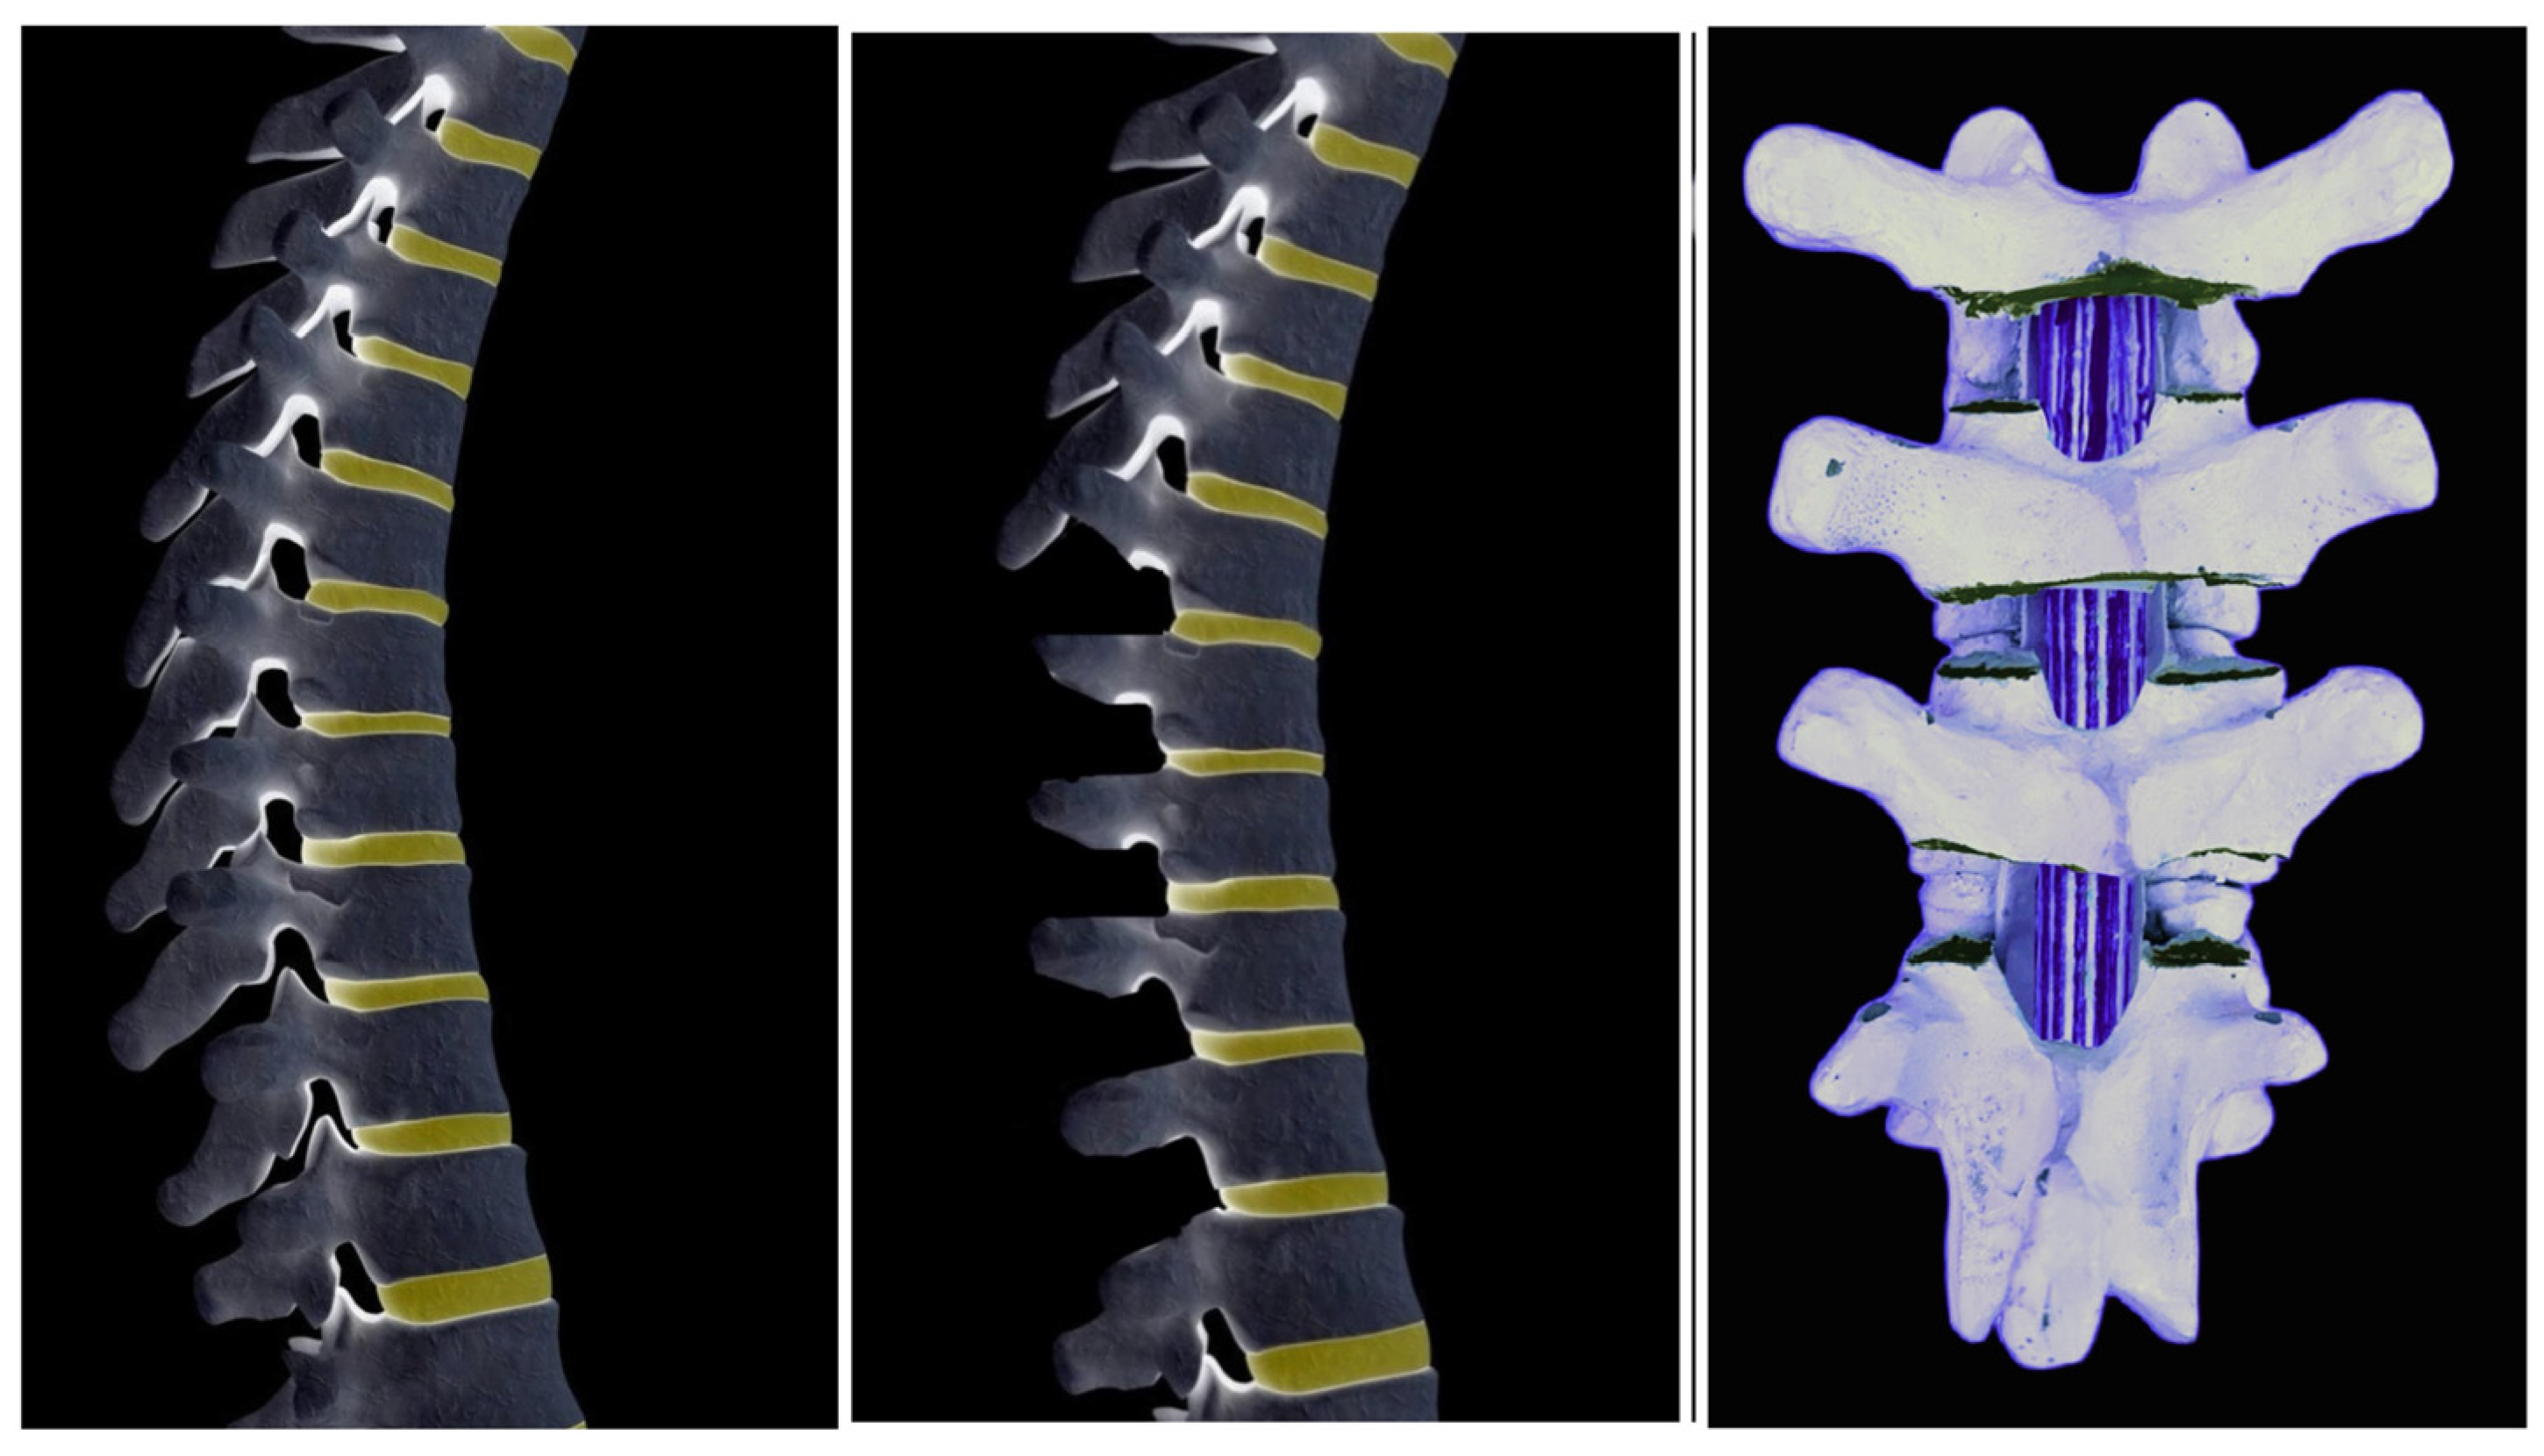

Severe scoliosis is characterized by bony changes that cannot be fully corrected through the release of soft tissues alone. When determining the appropriate osteotomy type to address this condition, several factors come into play. These factors include the extent of correction needed, the specific location of the deformity, the degree of imbalance in both the sagittal and coronal planes, the overall health status of the patient, and the expertise of the surgeon involved [19,26]. In numerous academic publications, the terms Ponte and Smith-Petersen osteotomy (SPO) are often used interchangeably, leading many surgeons to perceive them as identical surgical techniques. Despite this common misconception, it is essential to recognize that they are not entirely identical, and the resulting discrepancies need to be delineated and understood comprehensively. The discernible disparities between the two osteotomies manifest in various aspects, such as the type and extent of resections performed, the distinct anatomical locations for which they were originally devised (lumbar versus thoracic), and the classification according to Schwab’s Osteotomy Classification, with Grade 1 assigned to Smith-Petersen osteotomy and Grade 2 designated for Ponte osteotomy. SPO involves a precise resection of lumbar facet joints and the detachment of the ligamentum flavum from the inferior edge of the lamina and inferior articular process, without any resection of the laminae. When utilized for enhancing flexibility in thoracic kyphosis, the correction is achieved through a broad opening of anterior disc spaces and elongation of the anterior column. On the other hand, the Ponte osteotomy entails a broad resection of thoracic facet joints, laminae, and complete removal of the ligamentum flavum. In cases of thoracic kyphosis, the original indication, correction is facilitated by a significant reduction in the length of the posterior column, accomplished by closing the osteotomy gaps through segmentally applied and apically directed compression forces. The absence of lengthening in the anterior column resulting from extensive openings of anterior disc spaces helps maintain the immediate and long-term load-sharing capacity and stability of the corrective procedure. It is generally recommended to avoid using open-wedge osteotomies in the thoracic spine to prevent elongation of the thecal sac and the associated neurological risks. Ponte osteotomies, on the other hand, involve the posterior removal of superior and inferior facets, laminae, ligament flavum, and spinous processes to address scoliosis [19,26,72,73,74,75]. Figure 6, Figure 7 and Figure 8 depict the Ponte osteotomy release method.

Figure 6.

Ponte osteotomies involve posterior wide resection of superior and inferior facets, laminae, ligament flavum, and spinous processes.

Unlike SPO, Ponte osteotomy generally does not elongate or minimally elongates the anterior column of the spine, making it a safe option for thoracic spine procedures [19,26,72,73,74,75]. Thorough removal of laminae is imperative to mitigate the risk of spinal cord compression. Figure 9 shows a 13-year-old girl with severe scoliosis treated with multi-level Ponte osteotomies and following PSF.